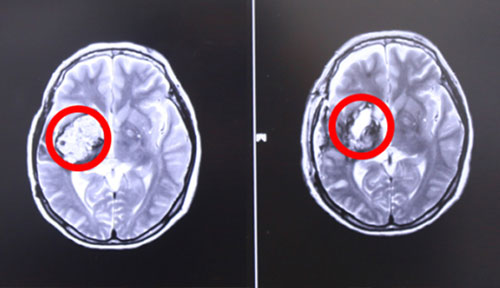

左侧为术前,右侧为术后,术后红圈内肿瘤物基本消失

17号上午9点左右,张XX被推入手术室,在全麻状态下接受“右颞顶海绵状血管瘤切除术”。至手术结束,已经日暮时分。手术由经验丰富的侯增欣主任主刀,上显微镜,分离侧裂,保护血管,切开颞上回皮质,见肿物呈暗褐色,靠近侧裂动脉,并向大脑深部丘脑生长,术中显微镜下肿物近全切除,手术顺利,脑神经及血管保护完好,患者全麻醒,返ICU病房进行术后监护。

术后,患者头晕症状好转,面部抽搐也未发作,肢体功能明显好转,生命体征平稳。据侯主任介绍,经过一段时间的康复,患者即可恢复生活自理能力。目前患者已经出院。针对此次案例,侯主任语重心长地说,作为一名神经外科医生,不仅要做好每一个手术,确保患者生命安全的前提下,尽可能全切肿瘤。更重要的是要针对每位患者的特殊情况特殊对待,拿捏好手术的度,不能一味保守或者冒进地对肿瘤不作为或不管不顾全切。侯主任根据自己临床多年的经验准确判断出病人损伤可以恢复,险中求稳求全,果断做了全切手术,从中我们也看到了一代专家的专业态度和敬业精神。